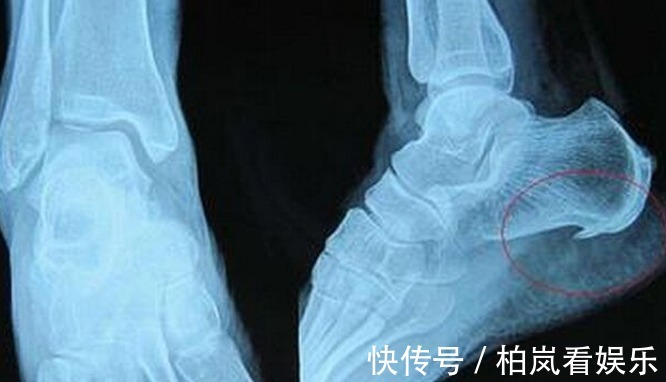

第二种:骨刺骨刺呢其实就是骨质增生。是关节因为种种原因而造成软骨的磨损和破坏。这是一种自然的老化现象,也是咱们人体的一种自我保护。骨刺呢,多发于在45岁以上的中年人或者老年人,而且男性要多于女性,久坐久站的话,也容易会提前诱发骨刺的发生。骨刺这种病,本身是无需治疗的。所以大家千万不要被一些胡乱吹嘘的广告给骗了。